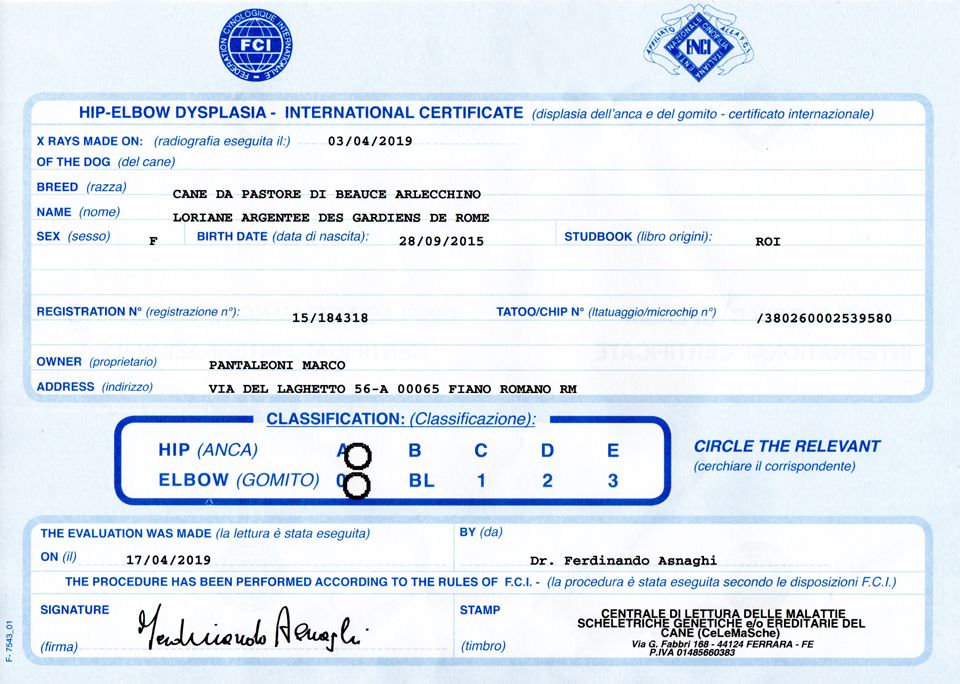

Loriane argentee Des Gardiens De Rome

femelle

Berger de Beauce

née le

28/09/2015

LORIANE Argentée des Gardiens de Rome

Informations sur Loriane argentee Des Gardiens De Rome

| Sexe | Femelle |

| Couleur | Arlequin |

| Puce | 380260002539580 |

| Inscrit au LOF ? | Italie |

| N° origine | LO15184318 |

| Statut | Retraité |